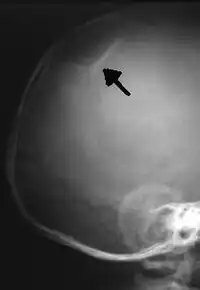

X-ray image of a depressed skull fracture in an infant. This injury is typical of child abuse cases.

It is alleged that proper diagnosis of plaintiff's condition would have included taking X-rays of her entire skeletal structure, and that such procedure would have revealed the fracture of her skull. Defendants negligently failed to take such X-rays, and thereby negligently failed to diagnose her true condition. It is further alleged that proper medical treatment of plaintiff's battered child syndrome would have included reporting her injuries to local law enforcement authorities or juvenile probation department. Such a report would have resulted in an investigation by the concerned agencies, followed by a placement of plaintiff in protective custody until her safety was assured. Defendants negligently failed to make such report.

On this appeal plaintiff has expressly abandoned her claim of punitive damages. It is alleged that proper diagnosis of plaintiff's condition would have included taking X-rays of her entire skeletal structure, and that such procedure would have revealed the fracture of her skull. Defendants negligently failed to take such X-rays, and thereby negligently failed to diagnose her true condition. It is further alleged that proper medical treatment of plaintiff's battered child syndrome would have included reporting her injuries to local law enforcement authorities or juvenile probation department. Such a report would have resulted in an investigation by the concerned agencies, followed by a placement of plaintiff in protective custody until her safety was assured. Defendants negligently failed to make such report. The complaint avers that as a proximate result of the foregoing negligence plaintiff was released from the San Jose Hospital without proper diagnosis and treatment of her battered child syndrome, and was returned to the custody of her mother and Reyes who resumed physically abusing her until she sustained traumatic blows to her right eye and back, puncture wounds over her left lower leg and across her back, severe bites on her face, and second and third degree burns on her left hand.